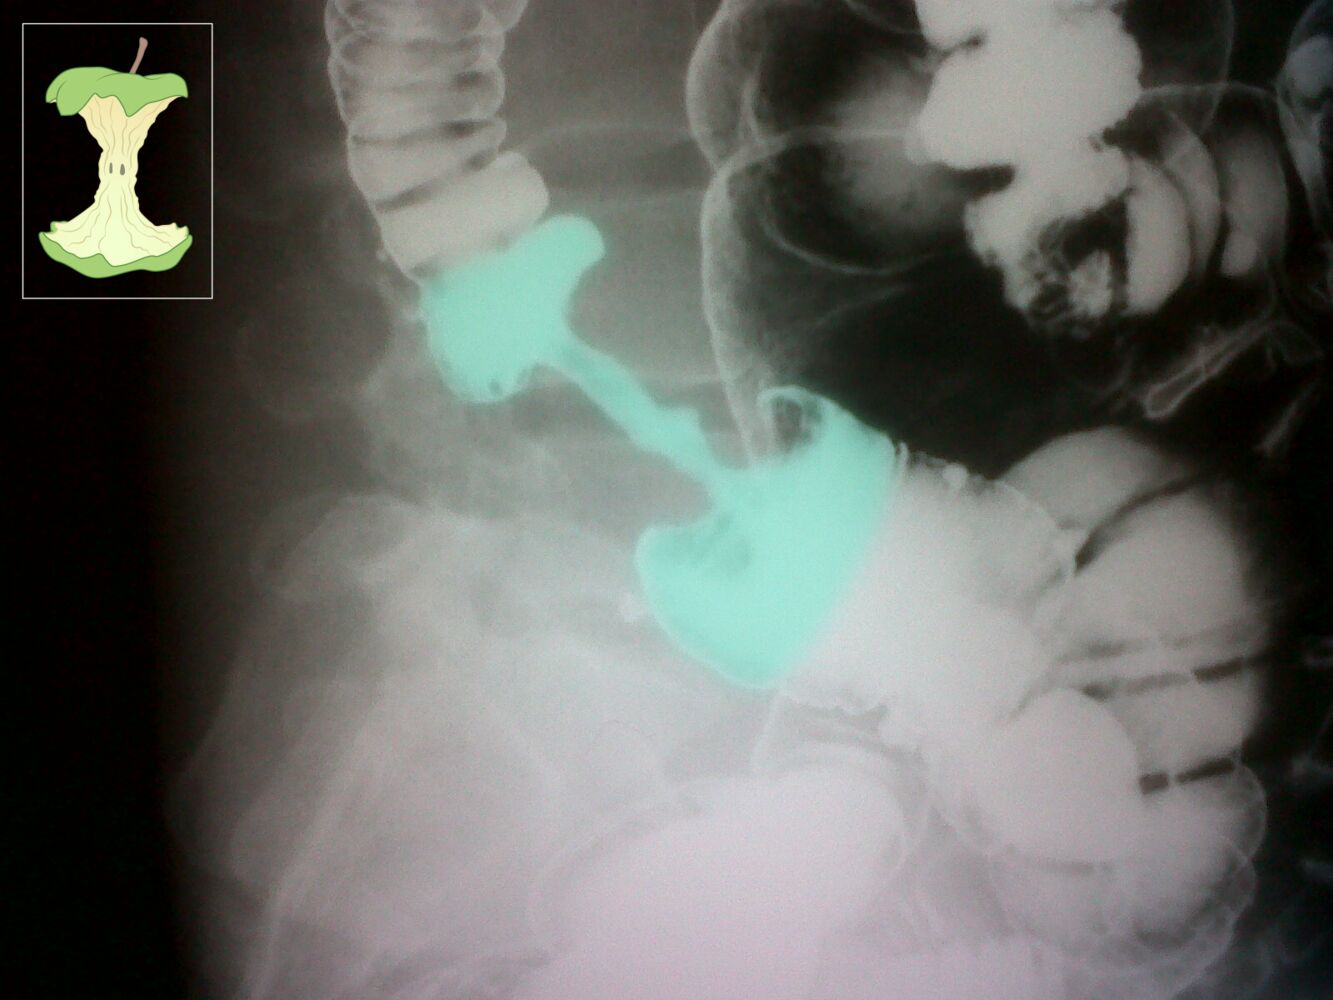

- Contrast radiography with enema (bird’s beak appearance in volvulus, Apple core sign in colonic malignancy)